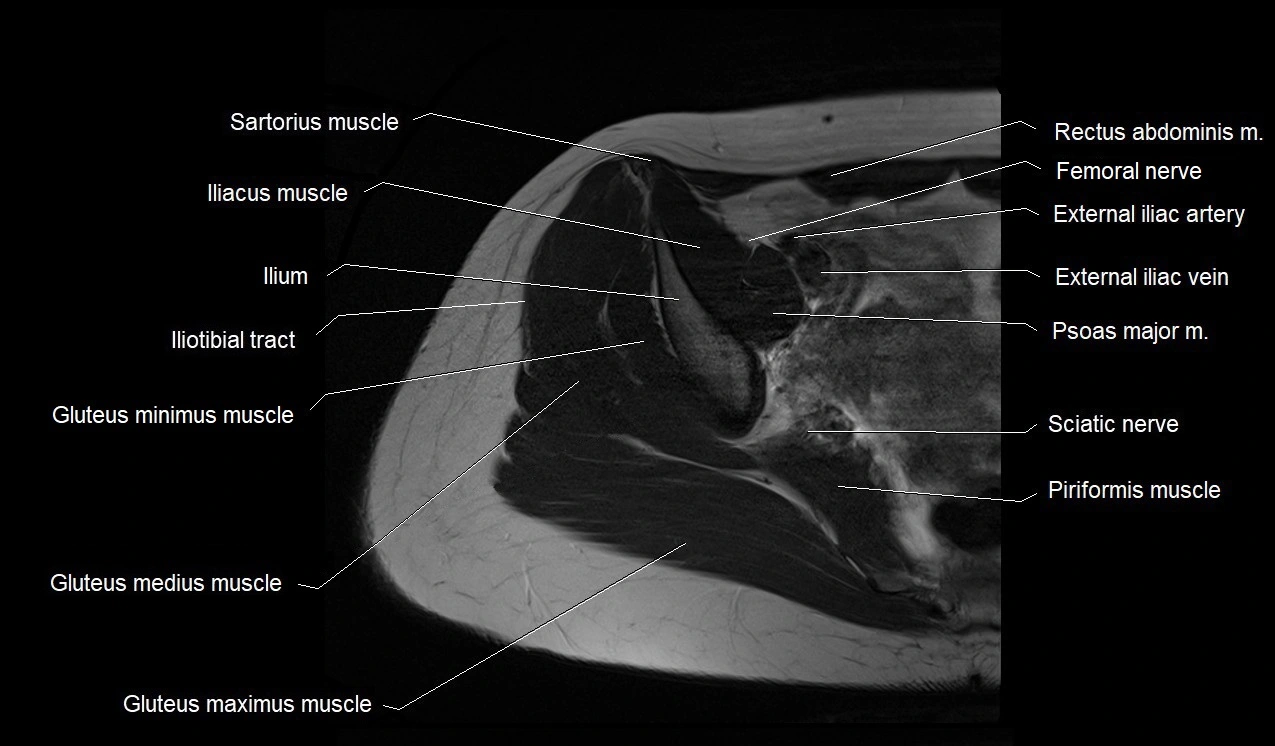

- Gluteus maximus muscle

- Gluteus medius muscle

- Gluteus minimus muscle

- Iliotibial tract

- Ilium bone

- External iliac artery

- External iliac vein

- Femoral nerve

- Sartorius muscle

- Iliopsoas muscle